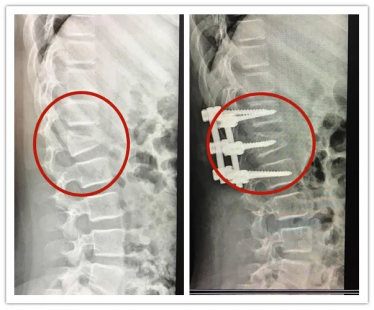

2020年7月,11岁的萱萱在家附近的游乐园玩蹦床,不知道是被其他小朋友撞到,还是自己没站稳,萱萱只记得自己高高弹起后屁股着地摔倒在蹦床上,“很痛。”

经CT检查显示,萱萱第一腰椎椎体爆裂性骨折,且存在明显的后凸畸形。好在手术很顺利,但萱萱需要躺着静养好一段时间,如果要下地行走,需要佩戴好保护支具。

萱萱手术前后